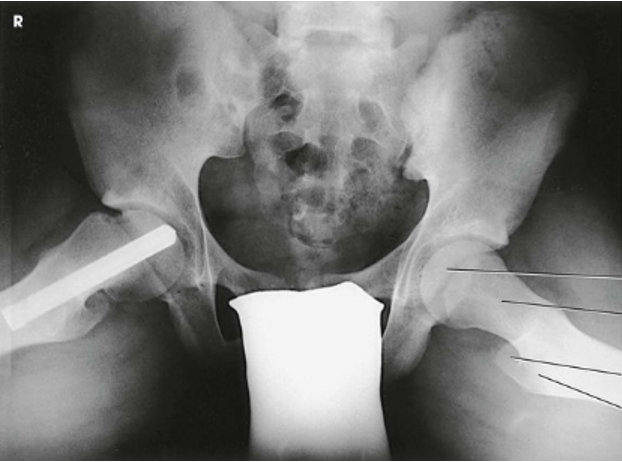

AP Oblique Projection; Proximal Femora and Femoral Necks; Modified Cleaves Method

AP Oblique Projection; Proximal Femora and Femoral Necks; Modified Cleaves Method (CR & SS)

The bilateral image shows an AP oblique projection of the femoral heads, necks, and trochanteric areas onto one radiograph for comparison

AP Oblique Projection; Proximal Femora and Femoral Necks; Modified Cleaves Method (Eval Criteria)

• Evidence of proper collimation

• No rotation of the pelvis, as demonstrated by a symmetric appearance

• Acetabulum, femoral head, and femoral neck

• Lesser trochanter on the medial side of the femur

• Femoral neck without superimposition by the greater trochanter; excess abduction causes the greater trochanter to obstruct the neck.

• Femoral axes extended from the hip bones at equal angles

• Soft tissue and bony trabecular detail